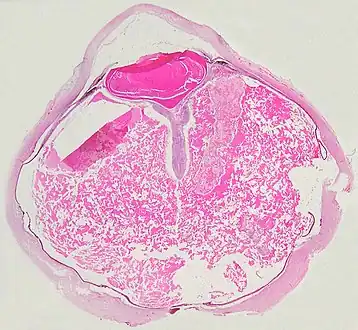

A case of Coats' disease, showing total exudative retinal detachment, and subretinal exudate containing cholesterol crystals (H&E)

Grossly, retinal detachment and yellowish subretinal exudate containing cholesterol crystals are commonly seen. Microscopically, the wall of retinal vessels may be thickened in some cases, while in other cases the wall may be thinned with irregular dilatation of the lumen.[10] The subretinal exudate consists of cholesterol crystals, macrophages laden with cholesterol and pigment, erythrocytes, and hemosiderin.[11] A granulomatous reaction, induced by the exudate, may be seen with the retina.[12] Portions of the retina may develop gliosis as a response to injury.